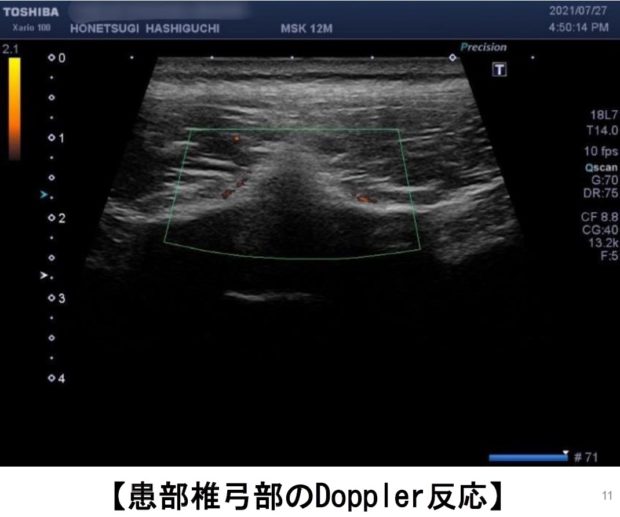

腰椎分離症が疑われる場合、はしぐち整骨院では、

で所見を観察することができます!![]()

(赤くなっている部分に血流が集まり炎症が起こっている状態)

(低エコーは、黒く見える状態のこと)